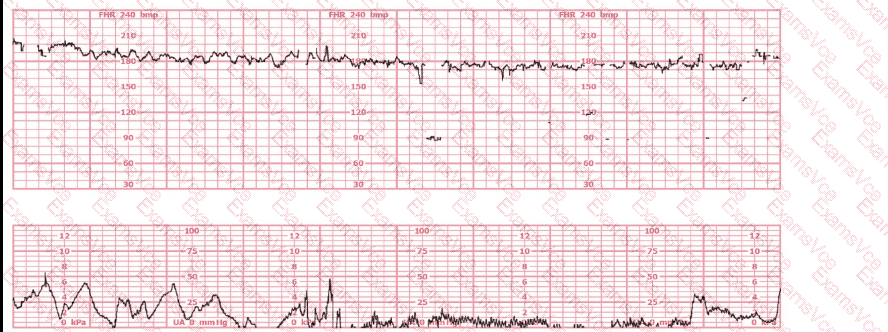

A 30-year-old woman (G2P0) is experiencing preterm labor at 26-weeks gestation. She is receiving magnesium sulfate for neuroprotection. Her external fetal monitoring tracing over the past 30 minutes is shown. The next step would be to: